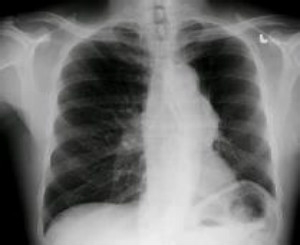

辐射:香烟中本身已含有了大量的致癌物质或有毒物质,已知的至少有250种,但现在最值得担心的是钋210,这是一种具有放射性的物质,如果每天抽1包半的香烟,一年下来,受到的辐射量相当于做了300次X光胸透片!

致癌:吸烟是肺癌的重要致病因素之一,特别是鳞状上皮细胞癌和小细胞未分化癌。吸烟者患肺癌的危险性是不吸烟者的13倍,如果每日吸烟35支以上,则其危险性比不吸烟者高45倍。吸烟者肺癌死亡率比不吸烟者高10~13倍。肺癌死亡人数中约85%由吸烟造成。

呼吸道受损害:吸烟是慢性支气管炎、肺气肿和慢性气道阻塞的主要诱因之一,长期吸烟可使支气管粘膜的纤毛受损、变短,影响纤毛的清除功能。